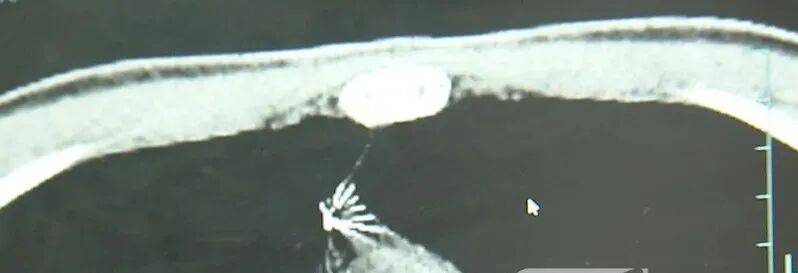

进一步的CT检查确认,异物是一枚金属针,斜插在肺组织内,位置十分凶险。